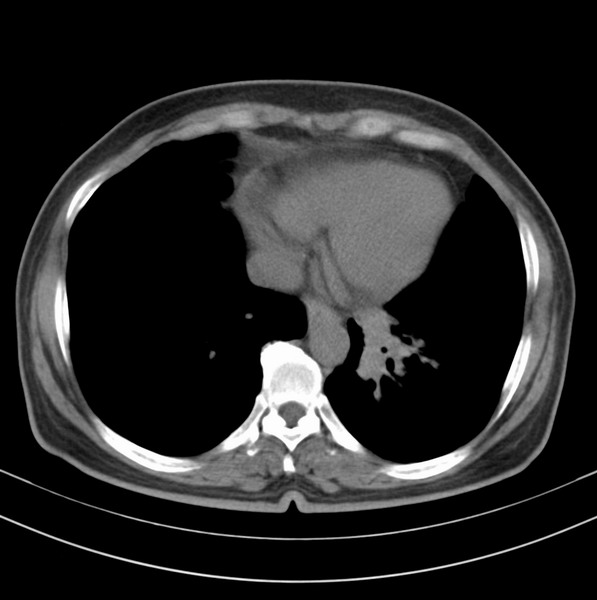

标题: CT20053:胸部增强请会诊。

女、63

咳嗽、胸痛四个月

包绕左下肺基底段的不规则的软组织肿块,段支气管腔变形、狭窄及阻塞性炎症,病变区不规则强化,又是老年女性支持楼上看法。

典型病例:左下肺基底段中央型肺癌,相应支气管狭窄并阻塞性炎症